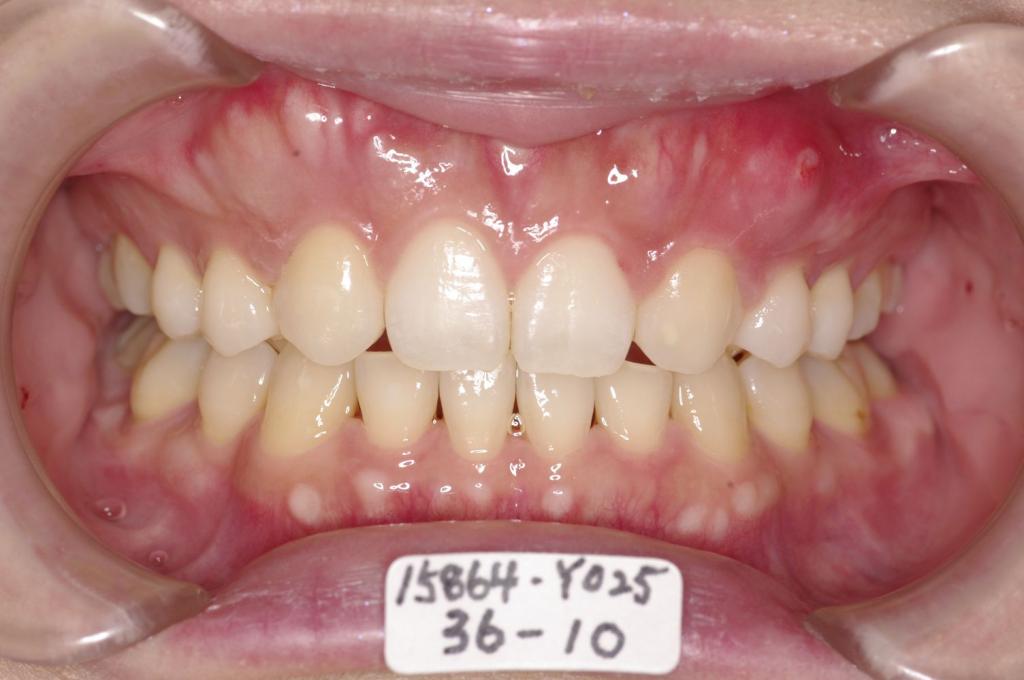

歯欠損の矯正治療

(治療期間、治療前後写真、治療方法、費用)WORKS

下記の実績データをクリックして頂くと「性別」、「治療開始年齢」、「治療終了年齢」、「治療方法(矯正治療装置写真含む)」、「治療終了までの費用」など、詳細な矯正治療データをご覧頂けます。